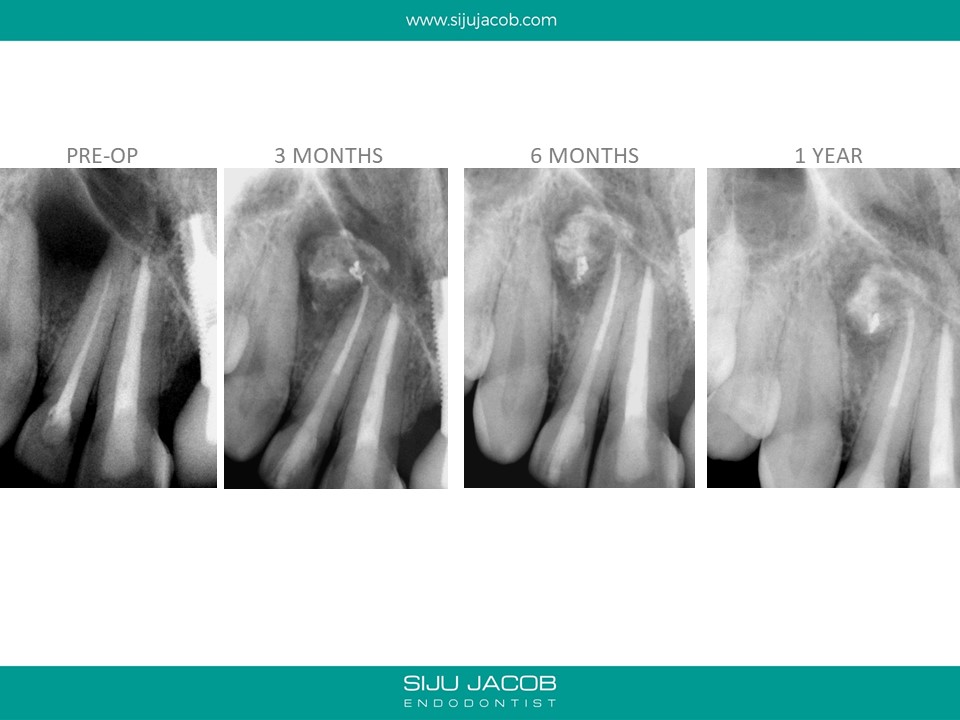

This patient was from The U.S. I re-treated a lateral incisor tooth of his while he was in Bangalore. He then went back to U.S. I received a mail from him two years later saying that the tooth we did was hurting. I thought that maybe, the lesion had recurred. I referred him to an Endodontist in the u.s who forwarded the radiograph to me. The lateral that I re-treated had healed well. It was an old central Incisor that had been treated much earlier that had fractured.